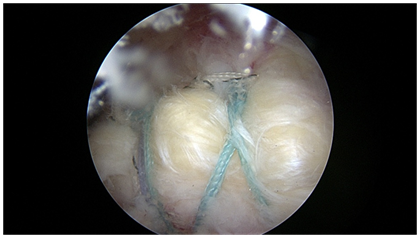

All transosseous techniques offer several permutations and combinations of suture patterns. The simple repair, the box repair, and the X box repair, are demonstrated in Figure 2. These techniques allow for multiple small diameter fixation points to create whichever fixation pattern the surgeon chooses as appropriate.

Figure 2 Various all transosseous repairs: a) simple b) X box c) three tunnel.